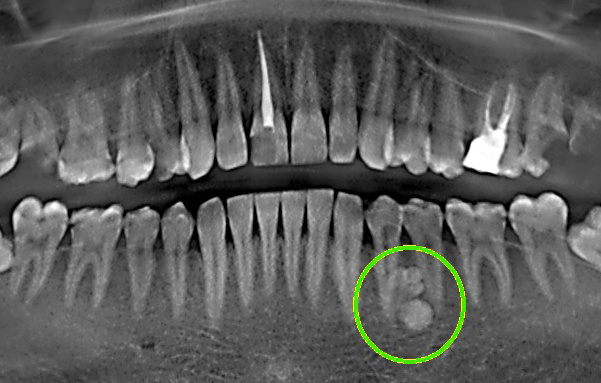

· Прицельная рентгенограмма (ортопантомограмма). Позволяет получить обзорную картину обеих челюстей и выявить наличие экзостозов. Этот метод наиболее распространен и доступен в стоматологической практике.